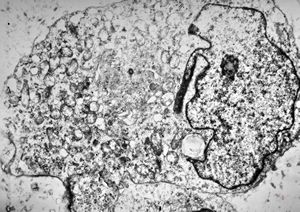

M,2m. | hypotonic syndrome - muscular atrophy